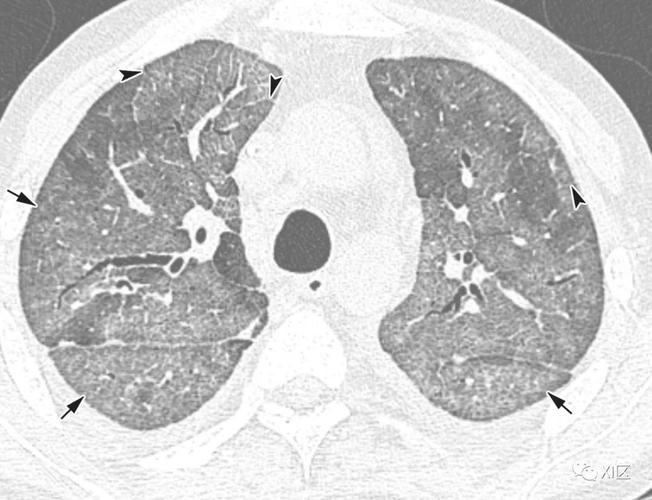

病毒性肺炎的影像学表现

病毒性肺炎CT